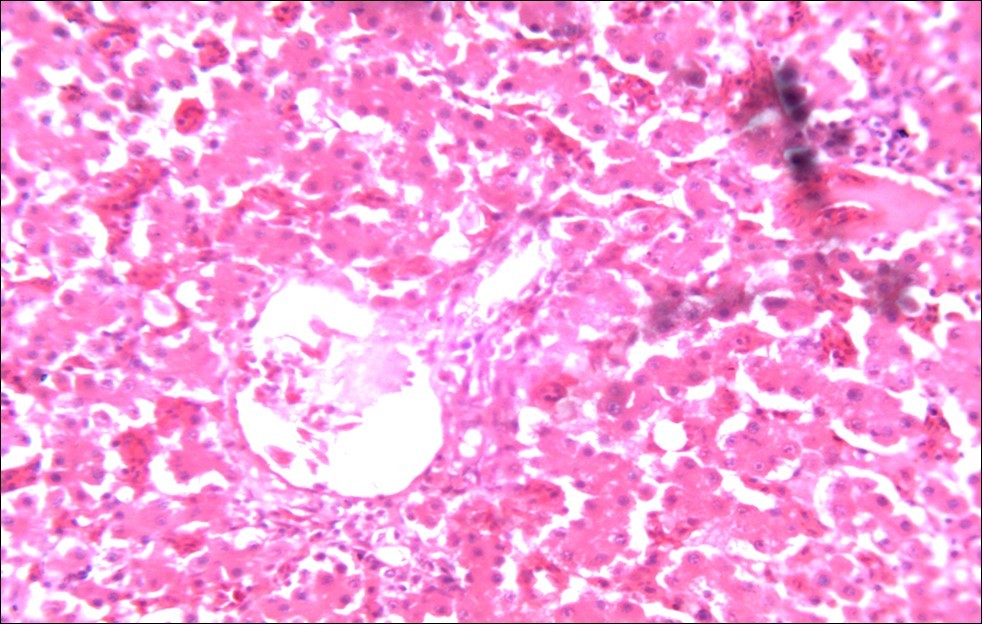

In addition, the generalized degeneration of the caecal glands, moderate numbers of gametocytes within the glandular regions with fibrosis which underscores reparative process in response to injury evoked by coccidiosis in the chicks which was perhaps brought about by the antioxidant and chemotherapeutic effect of NeemAzal®. The observed increase in RBC and hemoglobin concentration (Table 1) is indicative of the erythropoieticability of NeemAzal®, which is beneficial since the Eimeria parasite in the epithelia of the intestines causes bloody diarrhea and consequently anaemia. This finding is in consonance with 15 who reported an anti-anaemic effect of Khaya senegalensis on phenyl hydrazine-induced anaemia in rats. If the results of this study are juxtaposed with the results of the previous studies on potent antioxidant, hepatoprotective and mitigative role of methanolic extracts of Azadirachtaindica,in both natural and experimental infection with Eimeria species and can be deduced that, NeemAzal® could be said to be a potent antioxidant, chemotherapeutic and tissue protective agent. This study also answered a question on further study advocated to determine the maximum safe levels of neem supplementation because the higher doses, due to its bitterness, may show adverse effects on feed intake which will change the performance parameters of birds (Figure 6 and Figure 7) . Light microscopic inspection of hematoxylin and eosin-stained sections revealed that the epithelial cells of the Cecum were infected by E. tenella(Figure 3 and Figure 4). The results of the safety study showed that exposure of chickens to NeemAzal® at 200mg/kg body weight did not alter the histoarchitecture of liver and kidney (Figure 6 & Figure 7) which is similar to the work conducted in the same environment by a group of Scientists 34. It is therefore recommended that NeemAzal® could be used as a coccidiostat to replace the expensive anti-coccidiostats in the market.

Figure 6.Photomicrograph of liver of chick administered NeemAzal® at 200 mg/kg showing no observable lesion X250 (H & E)